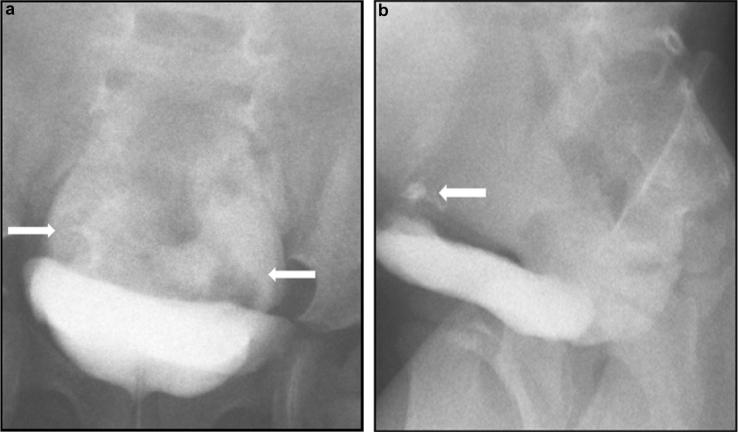

Idiopathic Urinary Bladder Perforation in Early Childhood.

Kidney Int Rep. 2018 Aug 3;3(6):1497-1500. doi: 10.1016/j.ekir.2018.07.022. eCollection 2018 Nov.